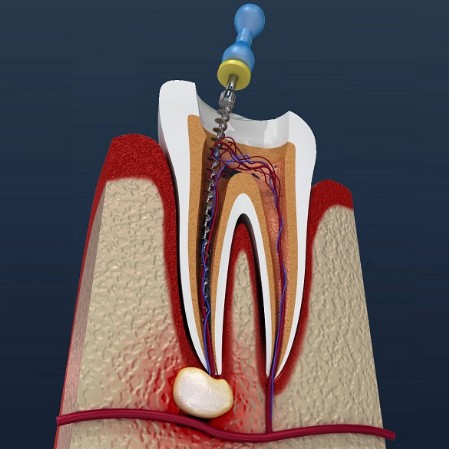

El tratamiento es conveniente cuando por algún motivo los conductos del diente son contaminados por bacterias, llegando a dañar el nervio, los conductos radiculares, la raíz o el hueso maxilar dónde se alberga el diente. Las causada principalmente para esta contaminación son por:

- Caries

- Dientes fracturados

- Lesiones periodontales

- Tallado protésico para la colocación posterior de coronas o puentes.

-Traumatismos dentarios